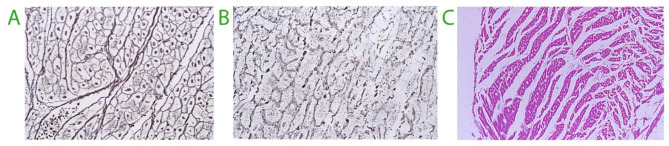

Main text: The skin, intestinal wall, and lungs are known primary locations of excess amounts of crystalloid fluid in humans. Microscopic studies in animals show that infusion of > 100 mL/kg of crystalloid fluid also causes interstitial dilatation and swelling of the heart, tissue breakup, and cardiac hypoxia. Volume kinetic analysis has identified several factors that promote peripheral edema during general anesthesia. Volume kinetics also shows that increasing volumes of crystalloid fluid sequentially expands three body fluid compartments: the plasma, a fast-exchange interstitial volume, and a more remote slow-exchange interstitial volume (in scientific jargon called "the third fluid space"). In settings of overhydration, the slow-exchange space operates as an overflow reservoir and quickly begins to accumulate fluid when the fast-exchange compartment has increased by 600-800 mL, which corresponds to infusing approximately 1.3-1.5 L of crystalloid fluid into the plasma over 30 min. Apart from overhydration, accumulation of fluid in the slow-exchange space occurs in inflammatory conditions, whereby cytokines and vasoactive molecules create a suction pressure that withdraws fluid from the fast-exchange space. This suction decreases lymphatic flow, causing hypovolemia and hypoalbuminemia in addition to peripheral edema. Preeclampsia and sepsis are examples of this complex kinetic situation. Albumin (20%), a hyper-oncotic colloid, might be used to modify peripheral edema by recruiting interstitial (lymphatic) fluid and stimulating diuresis.

Conclusion: Excess amounts of crystalloid fluid accumulate in body regions, such as the skin and intestinal walls, that have a high compliance for volume expansion. The heart is potentially a key trouble spot in severe overhydration. Accumulation of fluid in an interstitial fluid space that equilibrates slowly with the plasma volume occurs in settings of overhydration and inflammation. Pathophysiological mechanisms that explain the complications and fatal outcomes of overhydration are insufficiently known in humans.